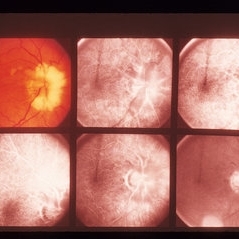

Feb 20 2013 by From the Collections of Thomas M. Aaberg, MD and Thomas M. Aaberg Jr., MD

Photo of an eye with myelinated nerve fiber around the optic nerve taken with a filter to show pseudofluorescence.

Condition/keywords: myelinated nerve fibers, pseudofluorescence